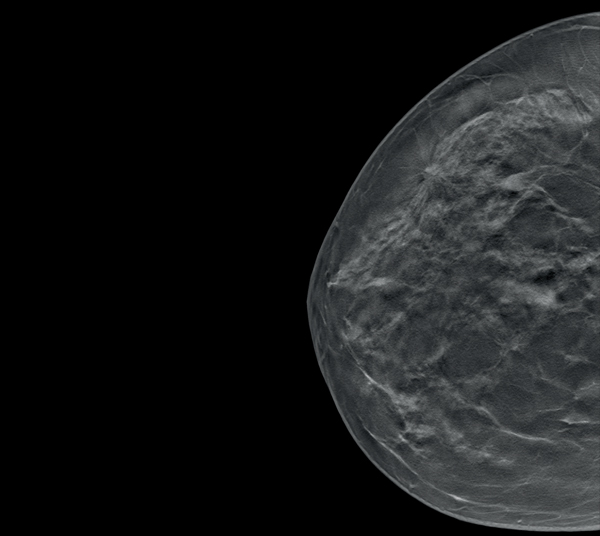

Η τομοσύνθεση του μαστογράφου SIEMENS επιτρέπει την καλύτερη διάκριση δύο σημείων και τη βέλτιστη ανάδειξη των χαρακτηριστικών μιας βλάβης με λιγότερες συμπροβολές και μεγαλύτερη ακρίβεια στη διάγνωση.

- Τομοσύνθεση Μαστού (3D απεικόνιση) Ευρείας Γωνίας (wide angle tomosynthesis). Μόνο το σύστημα Mammomat Revelation διαθέτει γωνία λήψης 50˚, τη μεγαλύτερη γωνία λήψης παγκοσμίως. Αυτό οδηγεί σε μεγαλύτερη ασφάλεια στη διάγνωση, αυξάνοντας τη δυνατότητα ανίχνευσης ακόμα και των πιο μικρών βλαβών στον μαστό, μειώνοντας τα ψευδώς θετικά ή αρνητικά αποτελέσματα και τις επανακλήσεις για επιπλέον συμπληρωματική εξέταση.

Απεικόνιση 2